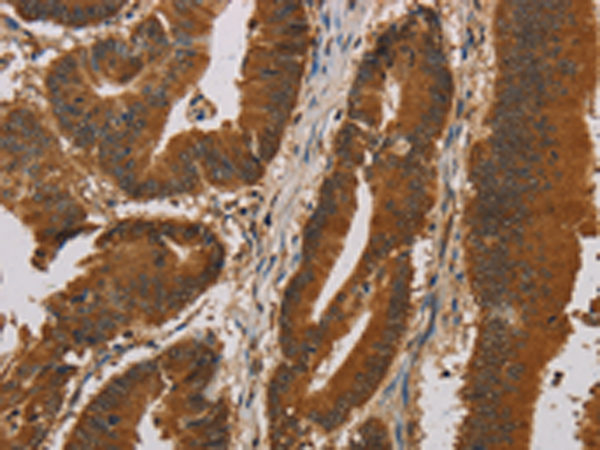

分类: 科研抗体货号: P11833别名: EPF; CPN10; GROES; HSP10应用: IHC反应种属: Human, Mouse, Rat